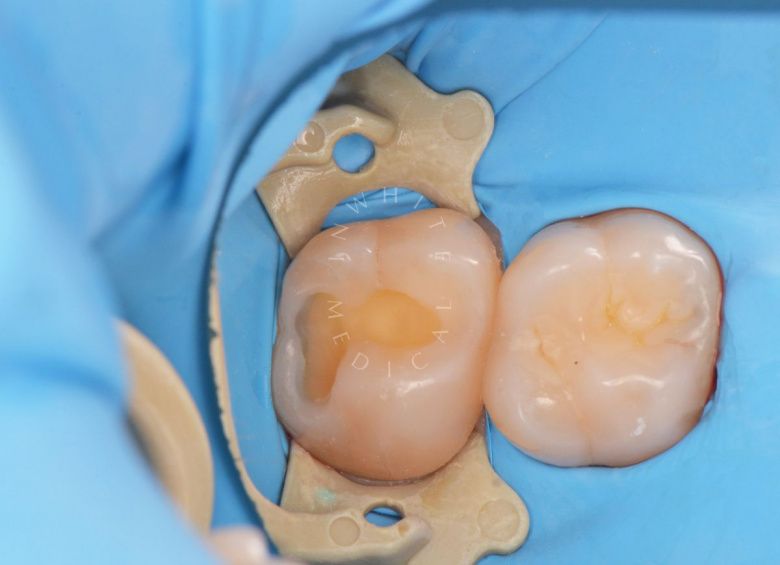

Лечение скрытого кариеса под старой пломбой

Лучшие стоматологические клиники. Лечение скрытого кариеса под старой пломбой  - после процедуры